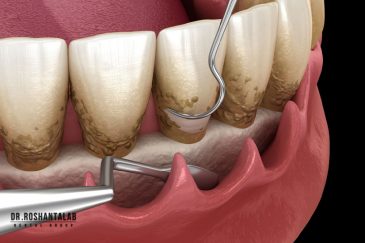

🔸 کاشت ایمپلنت دندان بدون درد

🔸کاشت ایمپلنت فلپ لس یا بدون جراحی و بدون بخیه زیر سه دقیقه

از عصب کشی و درمان ریشه دندان گرفته تا جراحی لثه و کشیدن دندان، تمامی مراحل توسط متخصص ترمیم دندان مدیریت میشود. ارائه باکیفیتترین خدمات ترمیم دندان برای سلامتی شماست.کاشت ایمپلنت فوری دندان